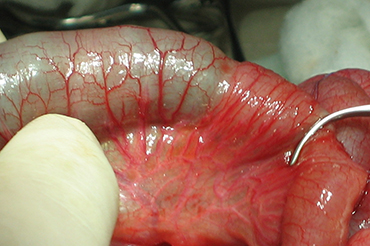

Atresia Intestinal

Neonatal y Lactante